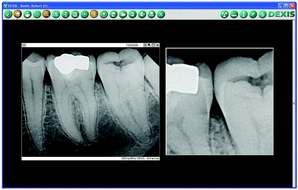

Next, is the benefit of greater understanding. Sensors yield digital images that can be enlarged and enhanced. Patients don’t really see or understand anything on a piece of film that’s 1" x 11⁄2". It is easier for patients to visualize conditions on large digital images. Then, the diagnosis and treatment you’re offering makes sense and is more willingly accepted.

Most importantly, there’s the added benefit of better diagnostics. Sensors capture images within imaging software. This software can open up a new world for you visually with image enhancements, magnification (Fig. 2), and measuring tools (Fig. 3). There’s even implant planning that calibrates a digital image for precise 2-D measurements (Fig. 4).